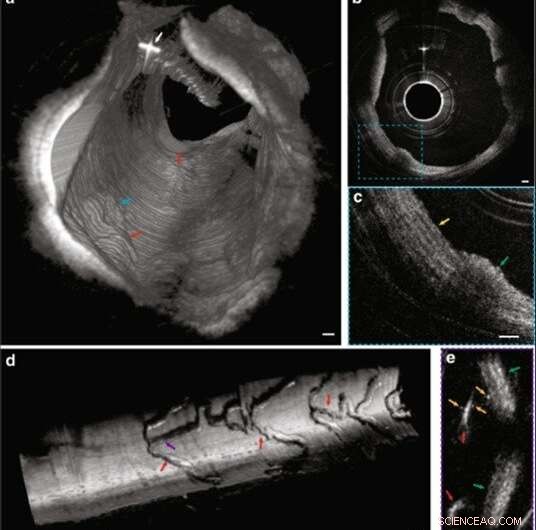

IVFMI images of rabbit arteries acquired in vivo. (a) 3D reconstruction of atherosclerotic rabbit aorta. The white arrow indicates the guide wire. The blue and red arrows indicate atherosclerotic plaque regions. (b) Cross-sectional image of the lumen wall that contains normal aortic media tissue and the atheromatous lesion indicated by the blue arrow in (a). (c) Magnified image corresponding to the blue dashed region in (b). The yellow arrow demarcates a region containing smooth muscle cells embedded in a collagen network in a portion of the normal aortic wall, while the green arrow indicates an atherosclerotic plaque. (d) 3D reconstruction of a stent implanted in the iliac artery. The purple and red arrows indicate stent struts. (e) A cross-sectional image corresponding to the location indicated by the purple arrow in (d). Orange arrows highlight tiny, punctate, highly scattering features that are consistent with platelets around the stent strut (red arrow), with the green arrows indicating the artery wall. A Gaussian blur filter with a radius of 2 μm was applied to the cross-sectional IVFMI images. Scale bar: 100 μm. Credit: Light: Science & Applications, doi: 10.1038/s41377-019-0211-5.

Using cross-sectional images, the team observed a network of collagen and smooth muscle cells in the normal media with improved clarity. They also obtained 3-D reconstructed IVFMI data at a segment of the lumen wall implanted with a stent an hour prior to imaging. The IVFMI process visualized microstructural detail of the stent struts with unprecedented detail for intravascular imaging. Yin et al. observed small, high-reflectivity, micron-sized dots surrounding some of the stent struts and could even identify the fine-detail of microstructural platelets in the images.